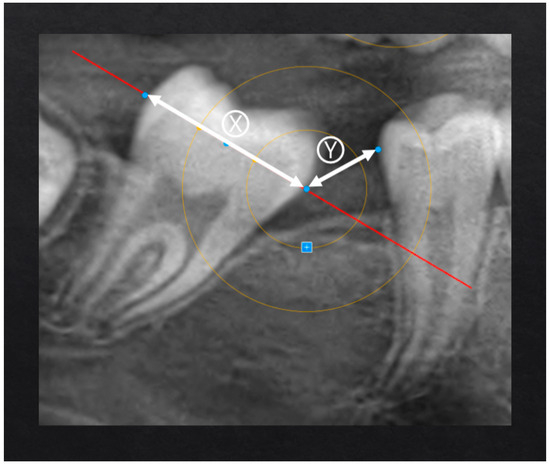

Spontaneous Second Molar Migration After MIH-Affected First Molars Extraction: A Radiographic-Based Method Evaluation

by Santo Andrea Stabilini, Lucia Giannini, Niccolò Cenzato, Francesca Olivi Mocenigo, Claudia Salerno, Cinzia Maspero and Maria Grazia Cagetti

Children 2025, 12(12), 1589; https://doi.org/10.3390/children12121589 - 23 Nov 2025

Background: Molar–incisor hypomineralization (MIH) represents a challenging dental condition, often requiring complex and invasive interventions. In severe cases, extraction of the first permanent molars (FPM) is frequently indicated. However, methods to assess the effectiveness of this approach in promoting spontaneous mesialization of the second permanent molars (SPM) through Orthopantomography (OPT), as well as the factors influencing this process, remain unexplored. Aim: This perspective study aimed to assess the effectiveness of novel radiograph-based methods for assessing spontaneous SPM mesialization after FPM extraction and to identify clinical and developmental factors associated with complete space closure. Methods: OPTs of 19 patients (12 males, 7 females; age range 6.2–13.8 years) who underwent extraction of 36 FPM due to severe MIH were analyzed by 2 operators. Pre- and post-extraction OPTs were evaluated using specifically developed geometric measurements of distances and angles to quantify SPM movement. Variables considered included patient age at extraction, dental developmental stage (Demirjian index), observation period, and presence or absence of the third permanent molar (TPM). The reliability of the proposed measurements evaluated through ICC (Intraclass Correlation Coefficient) resulted in values above 0.9, confirming excellent intra- and inter-operator reliability. Results: Complete or quite-complete mesialization (target scores 0–1 and ≤33% residual space) occurred in 78.6% of maxillary and 73.7% of mandibular sites. Maxillary SPMs showed more favorable spontaneous movement, exhibiting substantial uprighting (e.g., from −32° to 2°) and a higher frequency of complete or near-complete space closure (78.6% vs. 73.7% in the mandible). Developmental stages D–E of SPM were associated with successful outcomes. Conclusions: Early extraction of severely compromised first permanent molars (FPMs) can represent an effective treatment option to promote spontaneous mesialization of SPMs, particularly in the maxilla. The proposed radiograph-based measurement method demonstrated high consistency and reproducibility. Overall, this novel measurement approach may serve as a reliable and valuable tool for future clinical and research applications. Full article

Figure 1